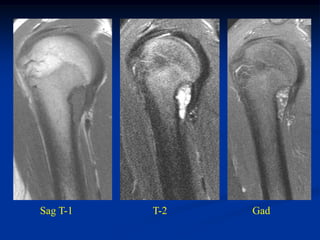

Case # 124.1                    AP and lat x-ray

50 year male with chondromyxoid fibroma proximal

tibia with 6 months of a tender tumor mass anterior tibia

Coronal T-1 MRI

Coronal PD FS MRI

Axial PD FS MRI

Axial Gad MRI